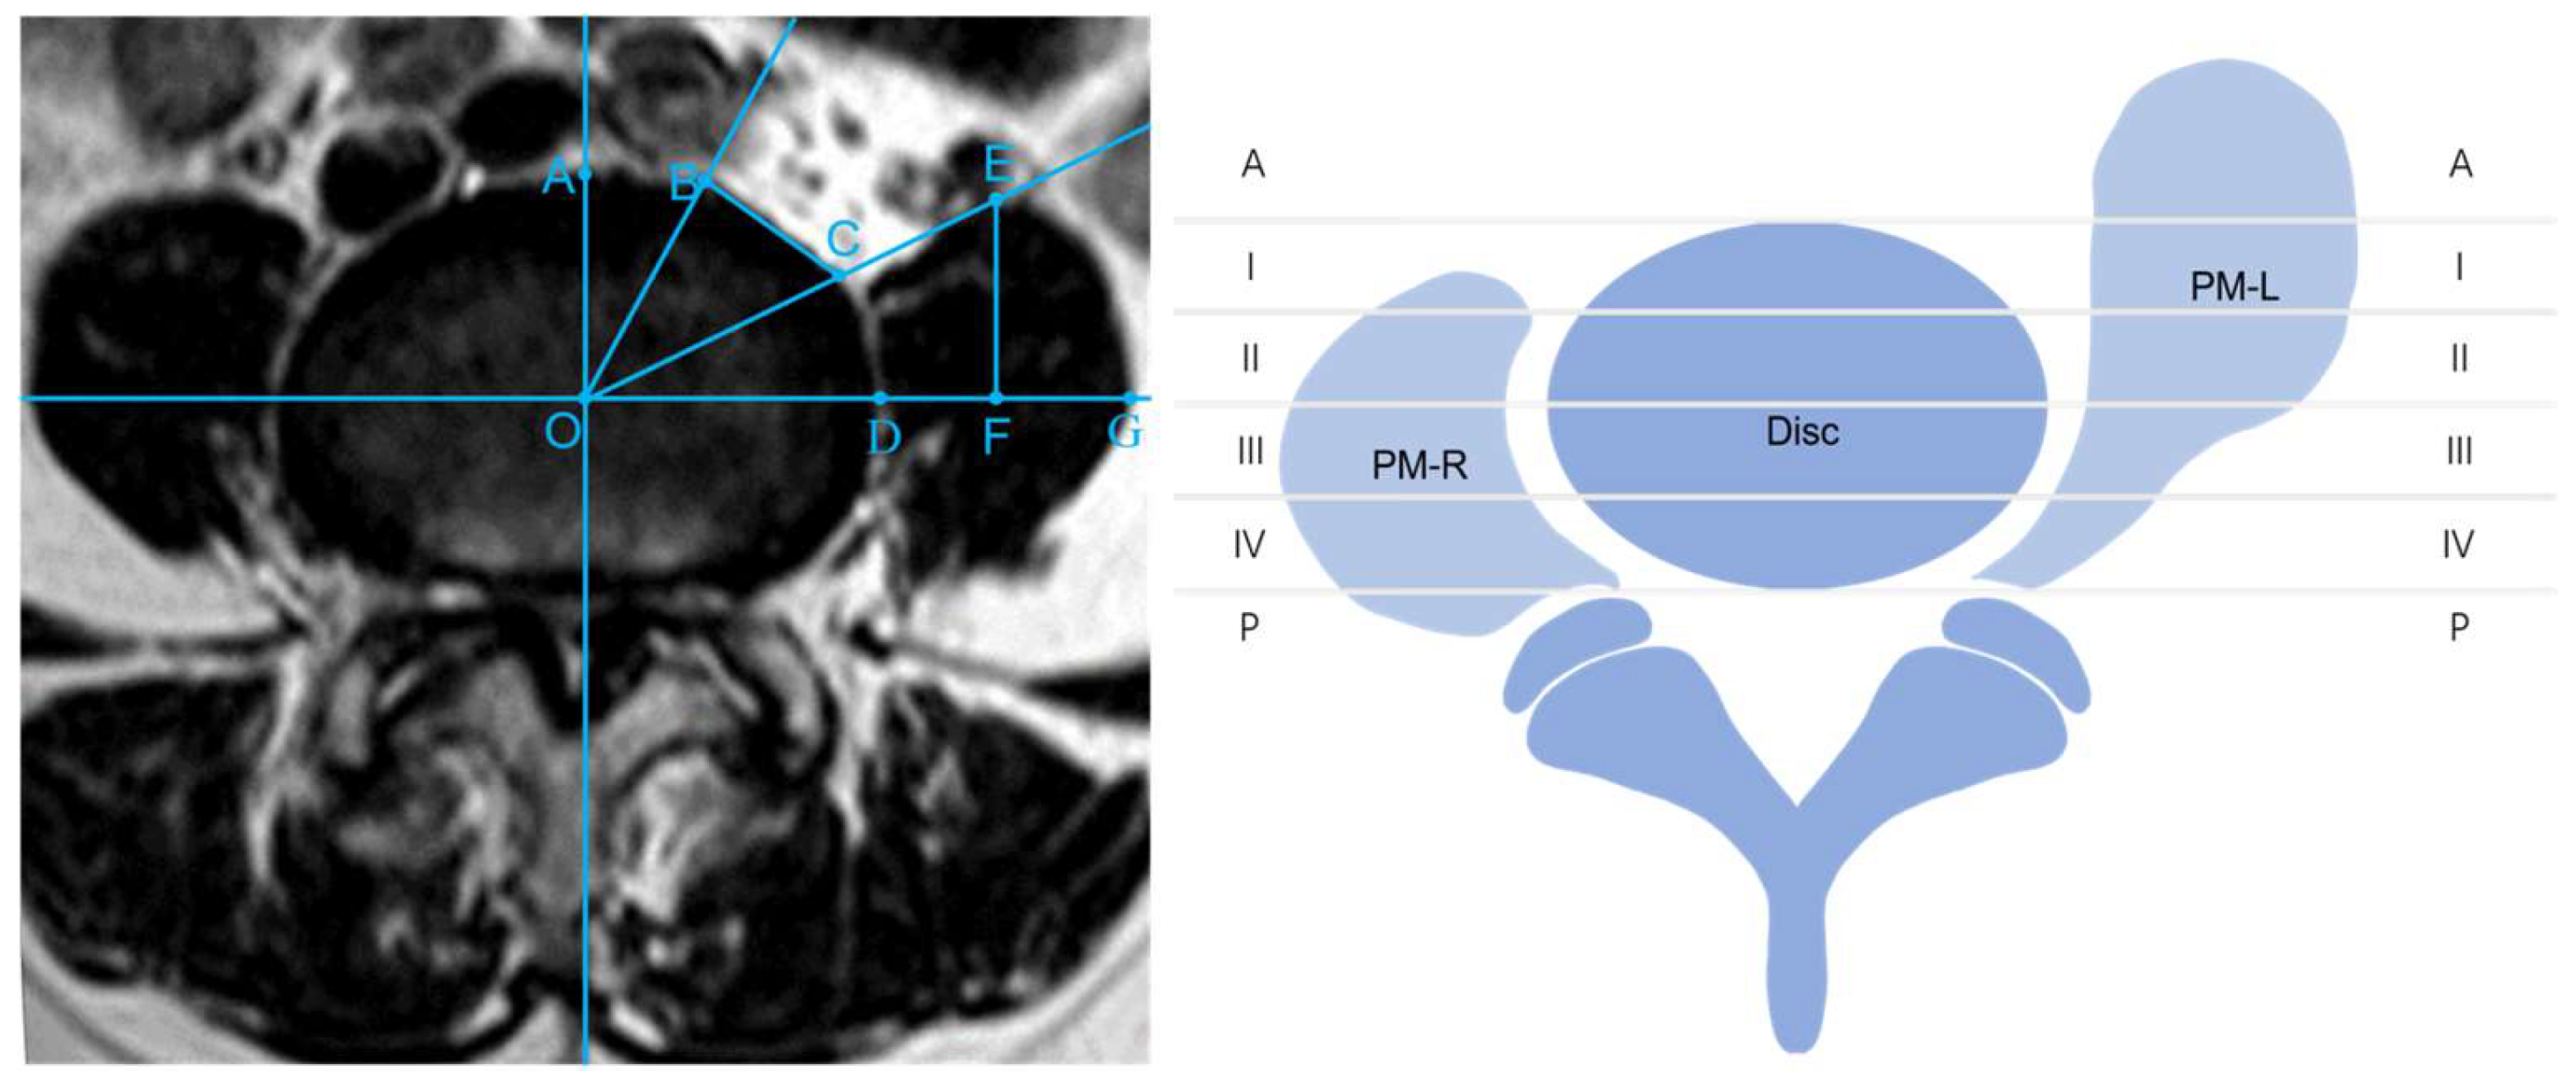

Preoperative and postoperative imaging parameters, including the disc sagittal diameter (DSD), operating window (OW), psoas major sagittal diameter (PMSD), and psoas major transverse diameter (PMTD) in all patients, were recorded based on the method of Chen X [13] (Figure 1 left). Postoperative imaging analysis was performed with MRI 1 week after surgery. Meanwhile, based on the method of Moro, the axial view of the intervertebral disc was divided into six regions, and the location of the left PM was evaluated [11]. Zones I to IV were of equal width. Beyond the anterior and posterior edge of the disc, the two regions were defined as Zone A and Zone P, respectively. The Moro zones of the PM were recorded, depending on whether the PM muscles were “teardrop-shaped” on MRI (Figure 1 right). Complications, estimated blood loss, and the length of hospital stay were noted. The operation time that we recorded did not include posterior percutaneous screw fixation (PPSF) because the PM needed to be retracted only in the oblique corridor. The visual analogue scale (VAS) and Oswestry disability index (ODI) scores were assessed postoperatively at 1 week, 3 months, 6 months, and 12 months.

Figure 1.

Measurement standards and Moro zones. (left): Disc midpoint (O); disc sagittal diameter, DSD (OA); operating window, OW (BC); psoas major transverse diameter, PMTD (DG); psoas major sagittal diameter, PMSD (EF). (right): The disc was divided into Zones A, I, II, III, IV, and P s. The psoas major muscles were divided according to the positions of their anterior borders. The left psoas major with a teardrop shape was located in Moro Zone A. The right psoas major with a normal shape was located in Moro Zone I.